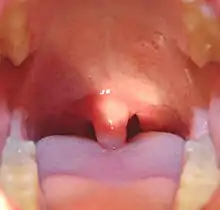

Palatine uvula

The palatine uvula, usually referred to as simply the uvula, is a conic projection from the back edge of the middle of the soft palate, composed of connective tissue containing a number of racemose glands, and some muscular fibers.[1][2] It also contains many serous glands, which produce thin saliva.[3] It is only found in human beings.[4]